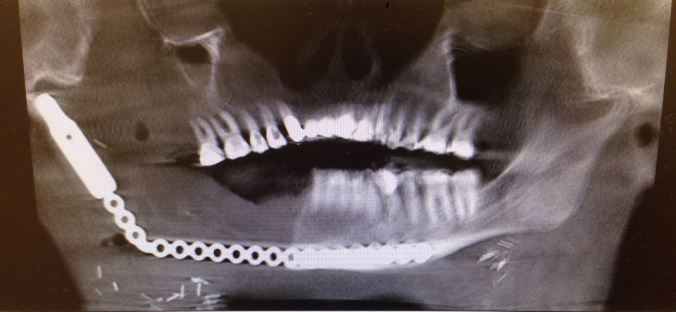

Now back to the less interesting part of this post. How do you like my new look? Yep, allow me to introduce you up close and personal to “robojaw.” This most recent scan shows my titanium implant.

Note the span. It runs from the socket by my ear all the way past the midline point of my chin. Just above the “chain” shows my remaining live bone in the mandible. Noticeable by their absence? All my teeth in that quadrant. Needless to say the left side does all the chewing work these days. I’m wondering if my dental hygienist will discount me 25% now at teeth cleaning time.